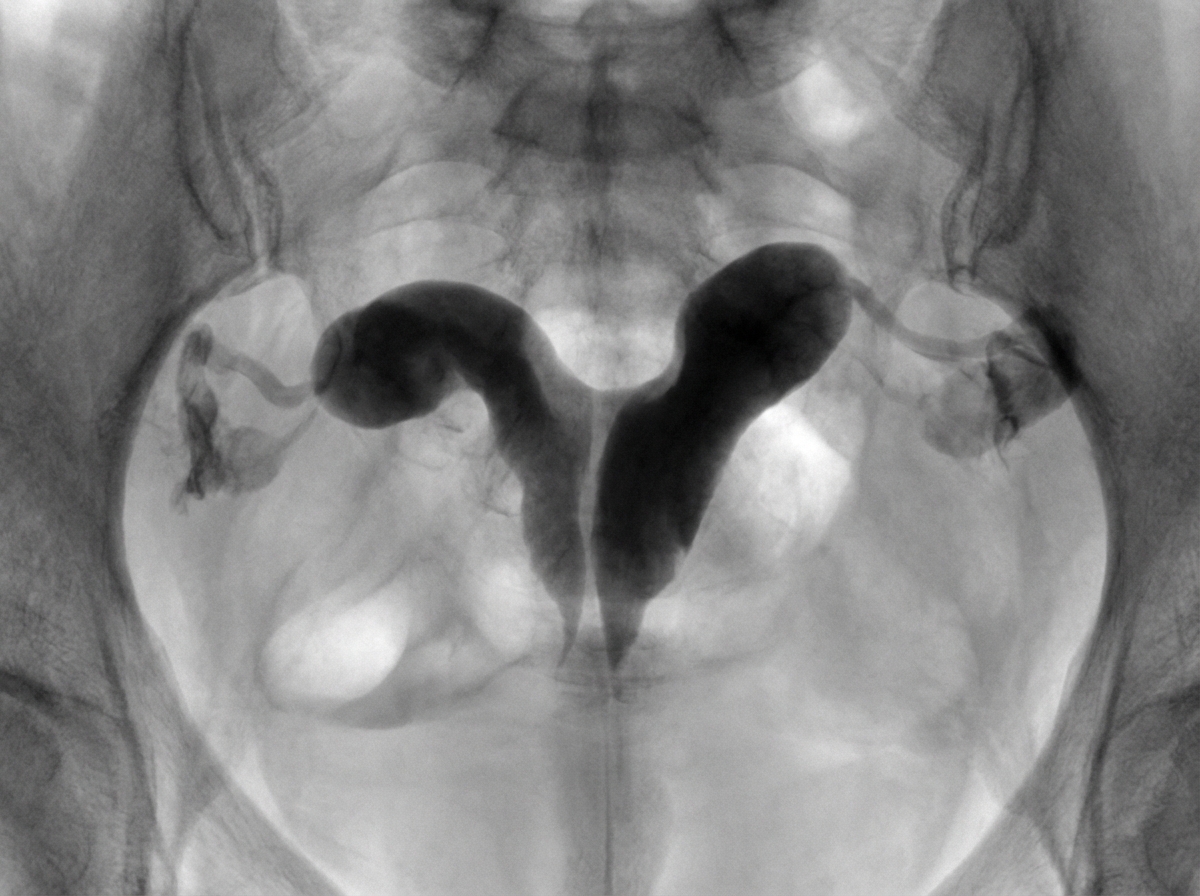

Diagnose the uterine condition shown on hysterosalpingogram.

Explanation: ***Bicornuate uterus*** - Shows **two diverging uterine horns** with a **fundal indentation >1 cm** and **intercornual angle >105°** on HSG. - Associated with **recurrent pregnancy loss** and **preterm delivery** due to reduced uterine capacity and abnormal contractions. *Unicornuate uterus* - HSG would show a **single horn** with **banana-shaped** or **comma-shaped** uterine cavity. - Often associated with **ipsilateral renal agenesis** and represents incomplete development of one Müllerian duct. *Arcuate uterus* - Shows a **mild fundal indentation <1 cm** with **intercornual angle <105°** on HSG. - Considered a **mild variant** with minimal clinical significance and lower risk of pregnancy complications. *Normal uterus* - HSG demonstrates a **smooth triangular uterine cavity** with no fundal indentation. - Shows **symmetrical fallopian tubes** with normal spillage of contrast into the peritoneal cavity.